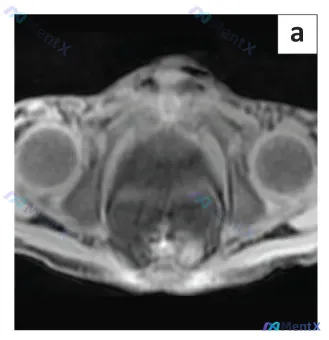

别被标签带偏!这张“眼部MRI”里竟然是前列腺?影像定位纠错与分析思路

起初拿到的信息是“眼部MRI”,但第一眼看到图像就觉得不对:解剖结构完全对不上。图像中央是一个盆腔脏器,膀胱底在前方,直肠在后方,两侧还有对称的股骨头——这明明是男性盆腔的轴位图像,核心展示的是前列腺区域。

📋答案:1. 图像定位纠错:这是一张**男性盆腔轴位MRI平扫图像**,而非标注的“眼部MRI”,核心显示结构为前列腺、膀胱底部、直肠及双侧股骨头。